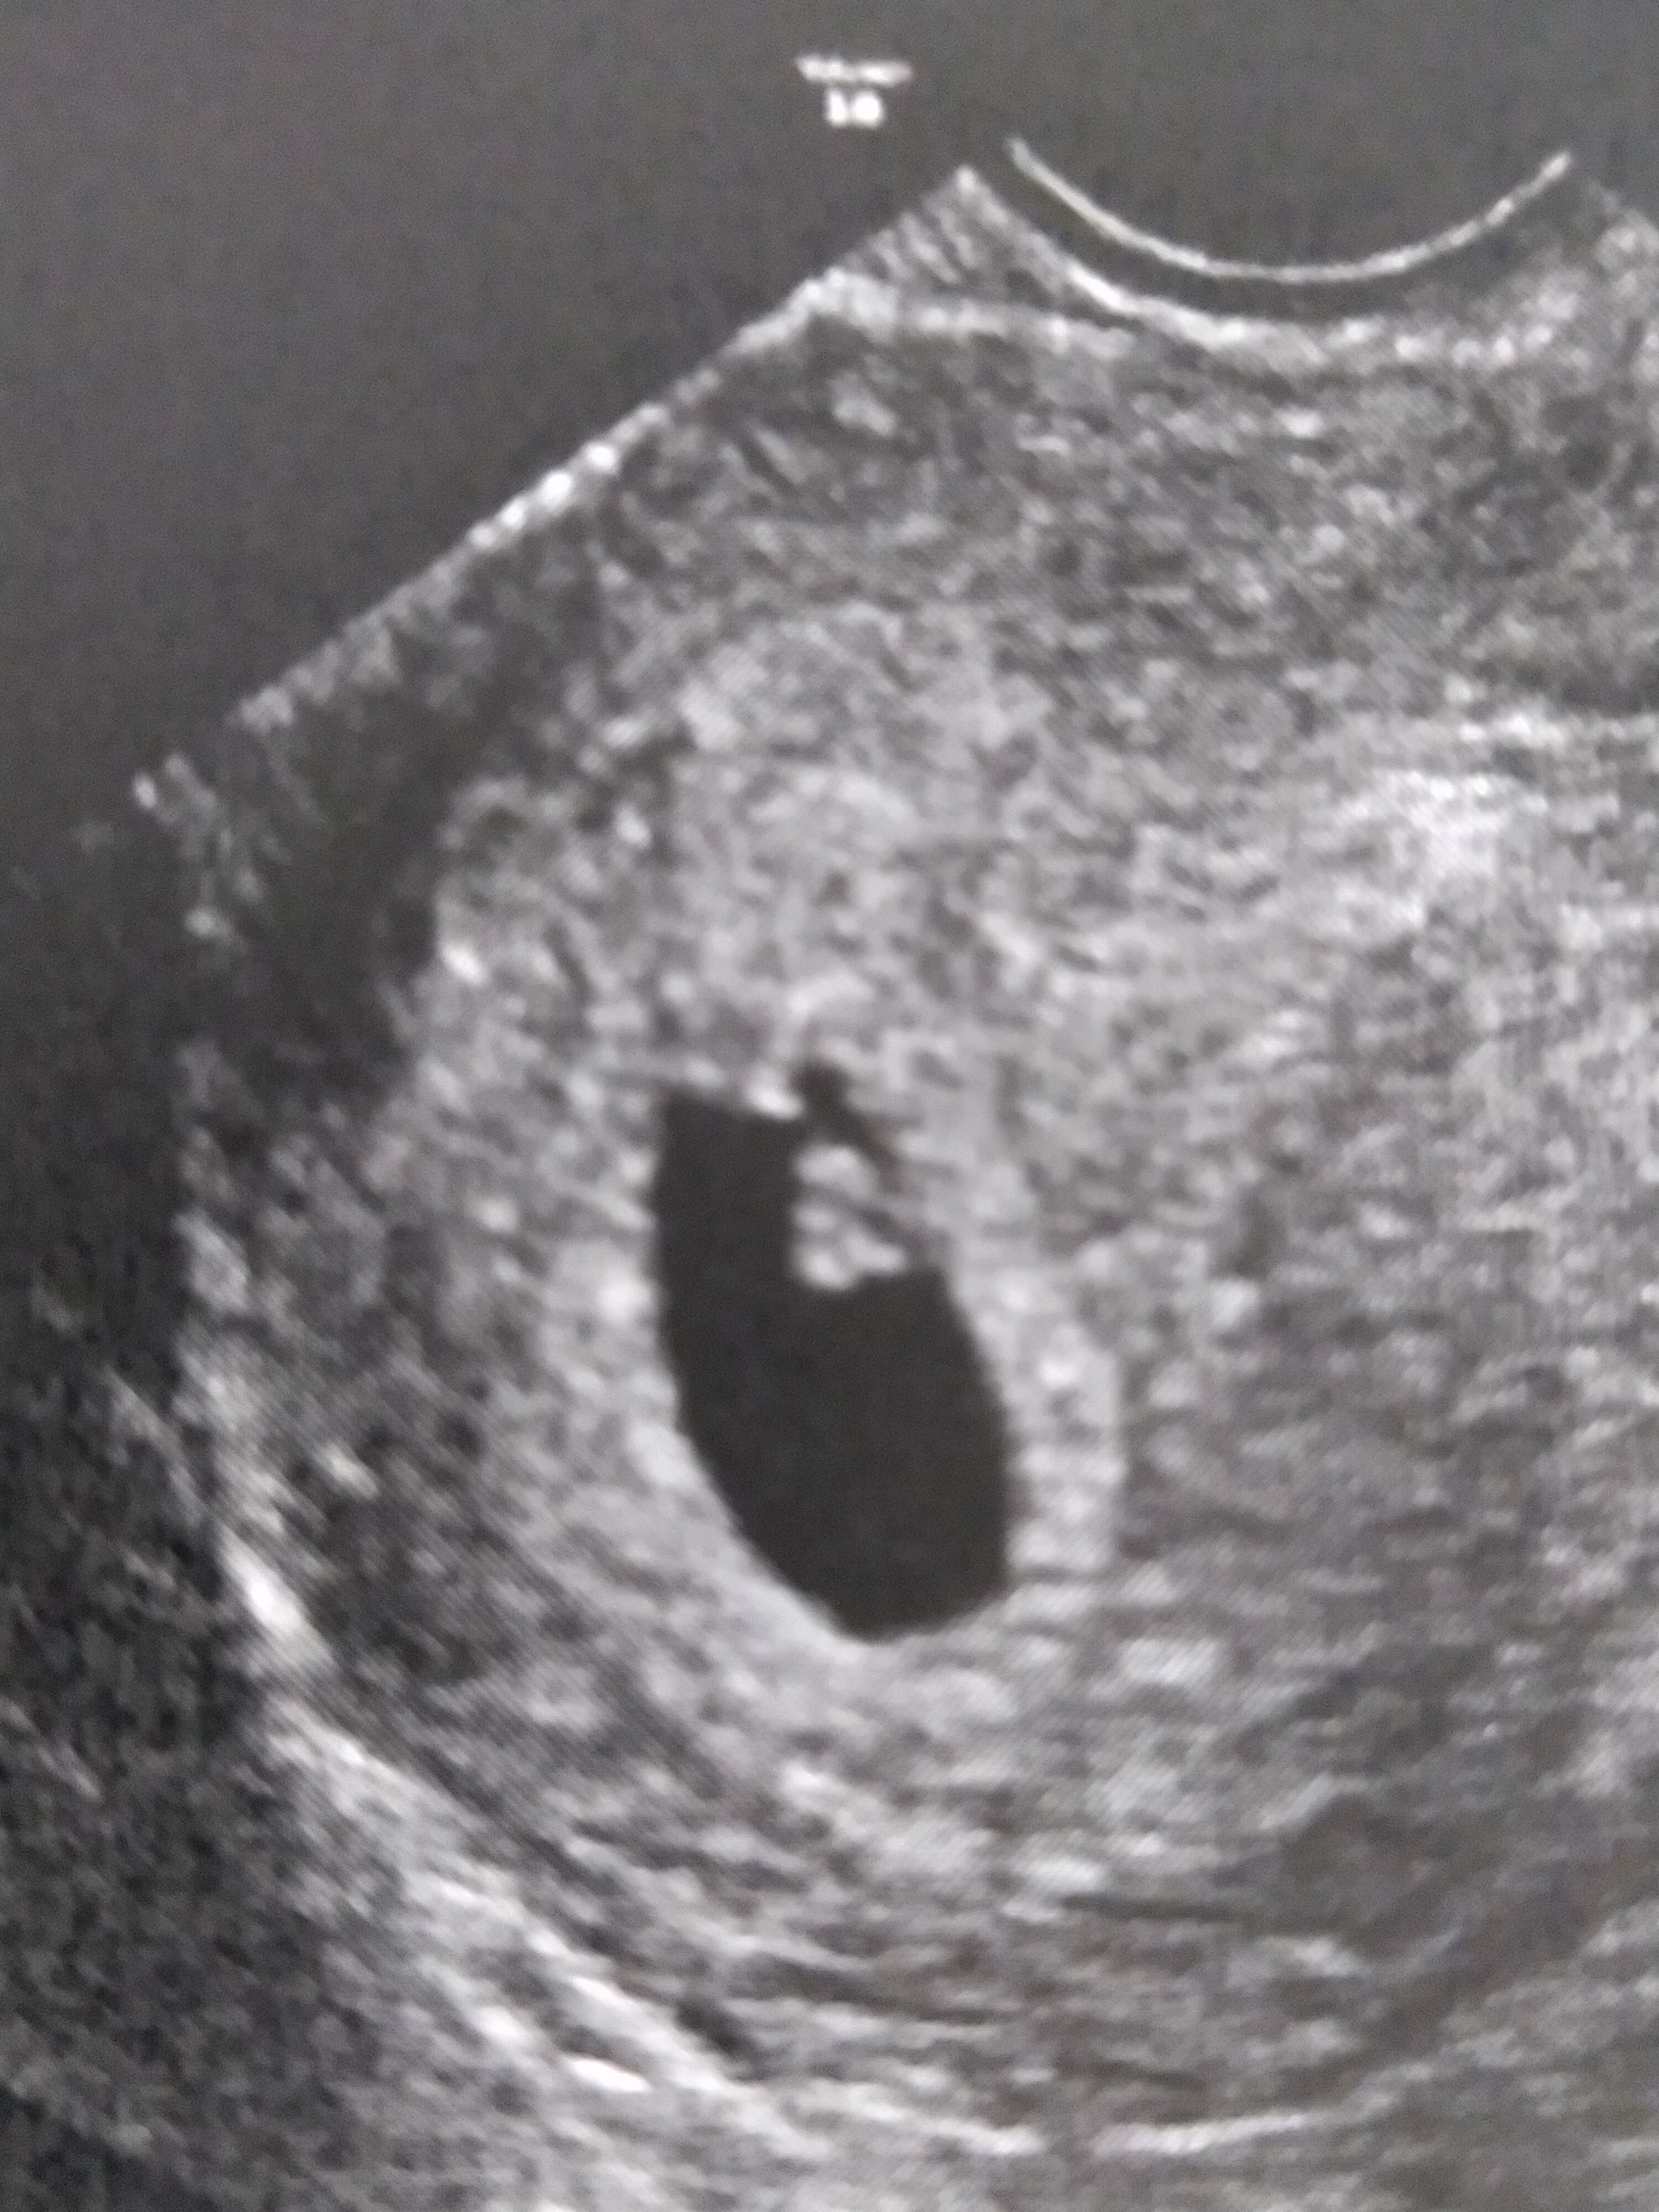

Dziewczyny mamy serduszko 😍

Jestem tak szczęśliwa, bałam się tak bardzo co zobaczę na USG, a pojawił się piękny mały człowiek 🥰

Dzisiaj wg om i USG 6t1d. Mierzy 0,43 cm i lekarz mówił, ze wszystko jest w porządku.

Wstawiam zdjęcie.